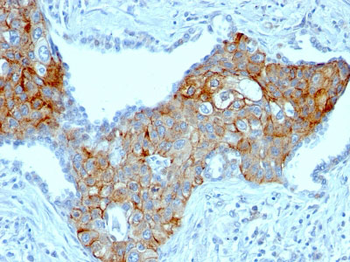

TRIM29 (Lung Squamous Cell Carcinoma Marker) Antibody

| Description | TRIM29 (Lung Squamous Cell Carcinoma Marker); Clone TRIM29/1041 (Concentrate) |

| Application notes | A431 cells. Tonsil or Squamous cell carcinoma. |